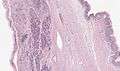

Pancreatic mucinous cystadenoma

Pancreatic mucinous cystadenoma, also known as "mucinous cystadenoma of the pancreas", is a benign tumour of pancreas. It is one of the cystic lesions of the pancreas.[1]

Microscopy

Mucinous cystadenoma of the pancreas